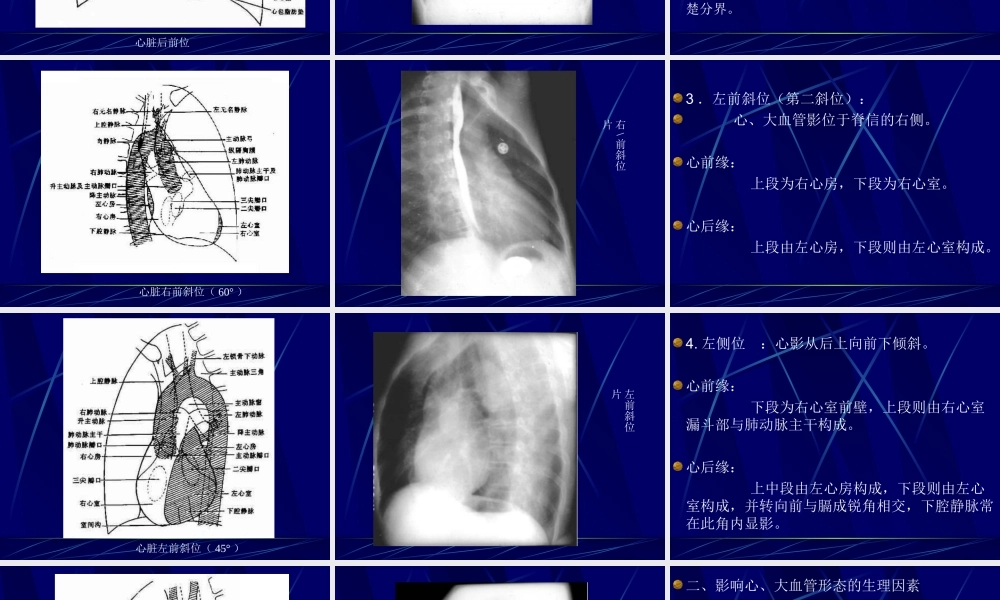

循环系统检查方法:透视:肺门舞蹈征(肺充血、肺A高压)相反搏动点(异常第三弓)摄片:常规四位片(后前位、左侧位、左前斜位、右前斜位)心血管造影:左心插管造影右心插管造影心脏投照常规四位片右心房──右左心房──后偏上右心室前左心室左正常X线表现:一、常规体位:1、后前位:心影2/3位于胸骨中线左侧,1/3位于右侧,心尖指向左下,心底部朝向右后上方,形成斜的纵轴。心右缘分为两段,其间有一明显的切迹。上段为升主动脉、无名静脉与上腔静脉。下段为右心房及下腔静脉所构成。心左缘分为三段:上段为主动脉弓、左心耳。中段为肺动脉段。下段为左心室、心包脂肪垫。心脏后前位后前位片2.右前斜位(第一斜位):心位于胸骨与脊柱之间。心前缘:自上而下由主动脉弓及升主动脉、肺动脉、右心室漏斗部、右心室前壁和左心室下端构成。心后缘:上段为左心房,下段为右心房,两者无清楚分界。心脏右前斜位(60°)右\前斜位片3.左前斜位(第二斜位):心、大血管影位于脊信的右侧。心前缘:上段为右心房,下段为右心室。心后缘:上段由左心房,下段则由左心室构成。心脏左前斜位(45°)左前斜位片4.左侧位:心影从后上向前下倾斜。心前缘:下段为右心室前壁,上段则由右心室漏斗部与肺动脉主干构成。心后缘:上中段由左心房构成,下段则由左心室构成,并转向前与膈成锐角相交,下腔静脉常在此角内显影。心脏左侧位左侧位片二、影响心、大血管形态的生理因素1.体型正常心可分横位心、斜位心和垂位心三种类型。矮胖体格体格适中体格瘦长2、体位平卧时膈升高,心上移,呈横位心。由于体静脉回流增多,上腔静脉影增宽,心影增大;立位时,膈下降,心影伸长;右侧卧位,心影向右侧偏移,右心房弧度加深;左侧卧位,心向左偏移,右心房弧度变浅,下腔静脉可清楚显示。3、呼吸:深吸气时,膈下降,心与膈面接触面减少,心影伸长,趋向垂位心。深呼气时膈上升,心呈横位心。4、年龄:3周以内婴儿心胸比率为0.55,7~12岁为0.5,与成人接近或相同,老年的胸廓多较宽阔,膈位置高,心趋向横位心。心胸比率:是心影最大横径与胸廓最大的横径之比。心最大横径取心影左、右缘最突出的一点与胸廓中线垂直距离之和,胸廓最大横径是在右膈顶平面取两侧胸廓肋骨内缘之间的最大距离。正常成人心影横径一般不超过胸廓横径的一半,即心胸比率等于或少于0.5。T1、T2:心横径,取心缘最突出部垂直于中线;T:胸廓横径,于右膈顶取水平线达两侧胸廓内缘;OO'...